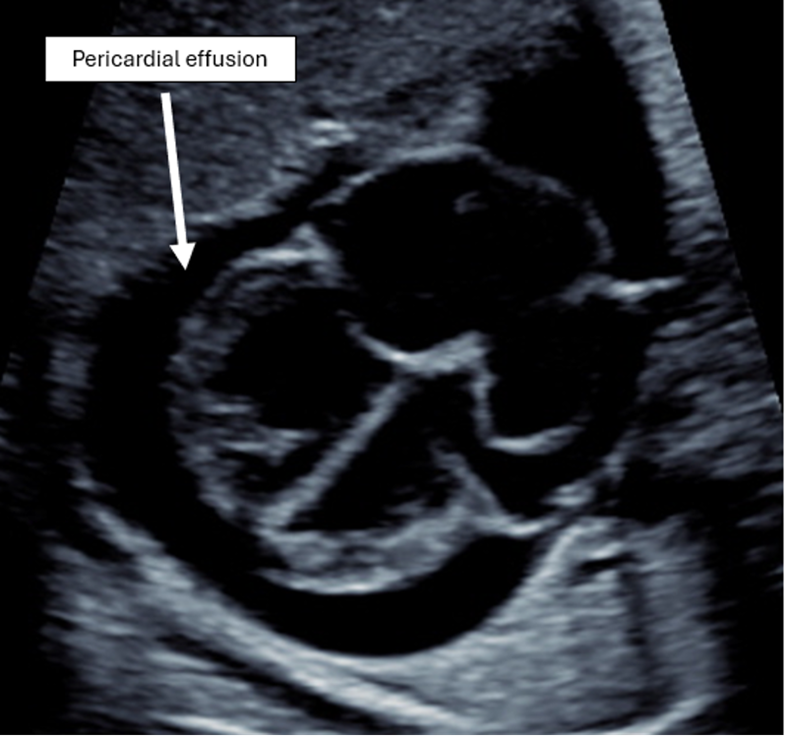

This fetus has a large, solitary, heterogeneous pericardial mass and a large pericardial effusion. Labeled frames from Video 1 are shown in Figures 1 and 2. These findings are characteristic of fetal teratomas.

Figure 1: 2D Imaging in an Axial Plane Demonstrating a Large Pericardial Effusion and Normal 4Ch Intracardiac Anatomy

2D = two-dimensional; 4Ch = four-chamber.